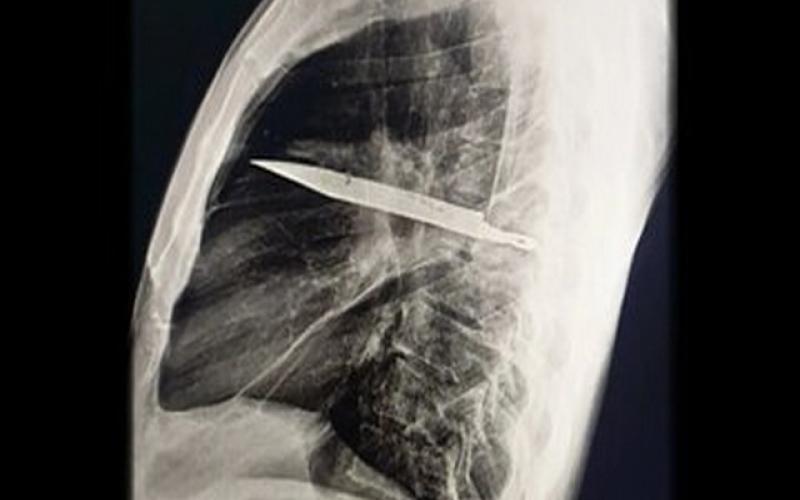

تصویربرداری با اشعه ایکس و سی‌تی‌اسکن نشان داد تیغه‌ای بزرگ از چاقو از پشت قفسه سینه وارد شده، بین دنده‌های پنجم و ششم گیر کرده و نوک آن تا جلوی قفسه سینه بین دنده‌های سوم و چهارم امتداد یافته است. شکستگی‌های ترمیم‌شده در استخوان کتف و چند دنده نیز مشاهده شد. هم‌چنین اطراف تیغه، بافت مرده و چرک تجمع یافته بود.